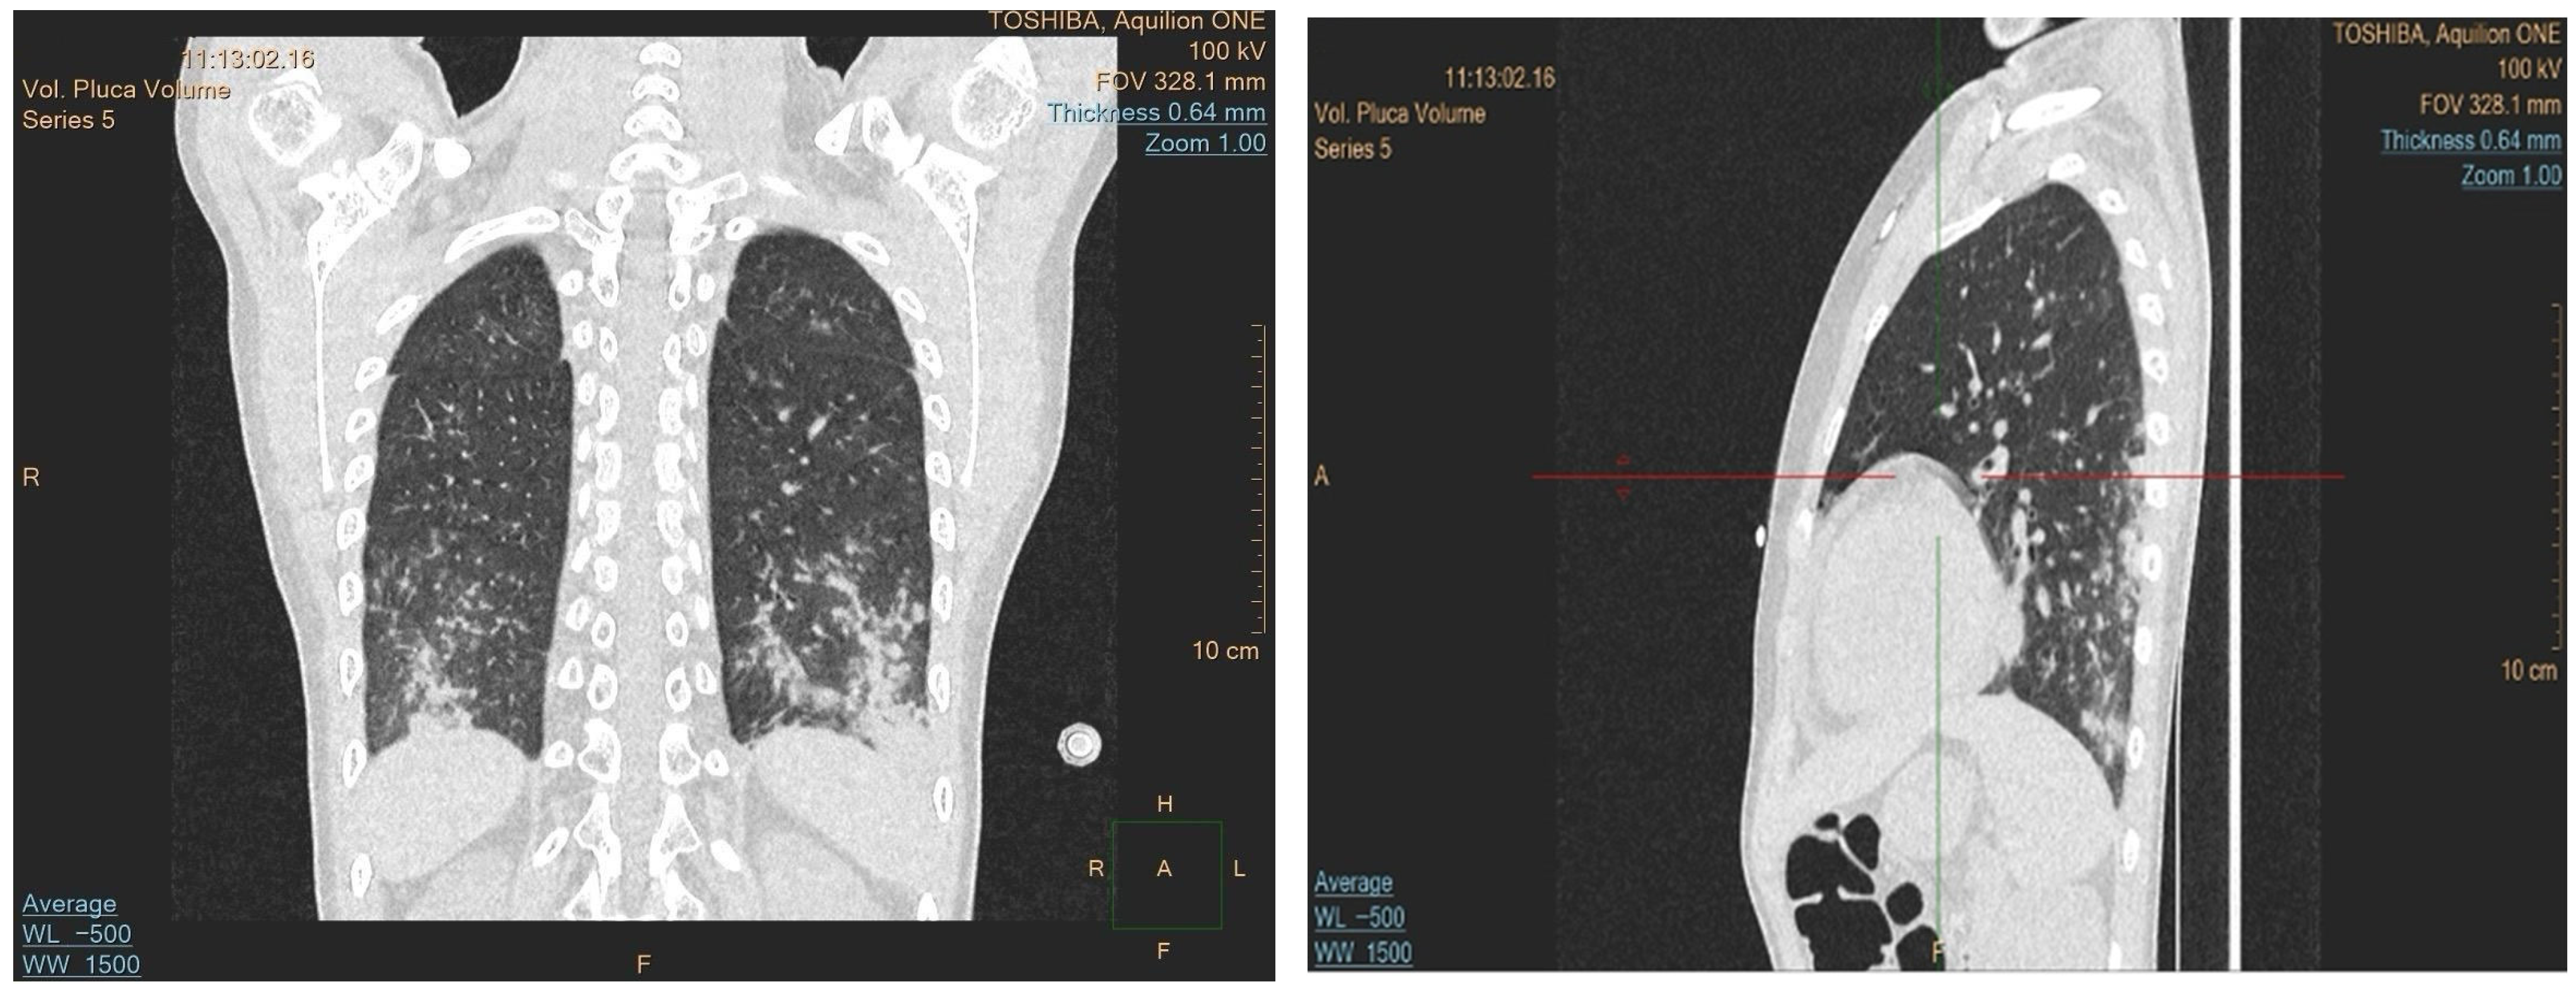

Due to the progression of the lung lesions observed in the follow-up imaging, amphotericin B was switched to isavuconazole. The patient also received broad-spectrum antibiotics and transfusions. A sinus MRI was performed to search for other potential sites of fungal involvement, which revealed suspected fungal changes in the left frontal sinus; drainage was performed, but no fungal growth was detected in the cultures. As the fever persisted despite antifungal and antibiotic treatment, an immunological cause was suspected. A control CT revealed progression of the lung lesions despite the antifungal treatment, which raised the suspicion of granulomatous lymphocytic interstitial lung disease (GLILD) (Figure 2). Bronchoalveolar lavage was performed, and the recovered fluid was sent for histopathological analysis and when stained using a Grocott stain showed no signs of fungal involvement, and no acid-fast bacteria were observed. However, cytology of the specimen showed 56% lymphocytes, 29% macrophages, 14% neutrophils, and 1% eosinophils. These histopathological findings, along with ground-glass infiltrate in a chest CT, helped diagnose the patient with GLILD, and the patient was subsequently treated with rituximab.

Due to immunosuppression caused by the underlying disease and the treatment, the initial lung infiltrates observed on the CT were treated empirically with antifungals. However, the progression observed in follow-up imaging raised suspicion of GLILD, and the antifungals were switched to rituximab. GLILD is diagnosed based on a combination of compatible high-resolution CT findings, characteristic lymphoid and granulomatous histopathology, and exclusion of infection and malignancy [13]. While GLILD is primarily associated with common variable immunodeficiency, rare cases have linked it to GATA2 deficiency [5], making it an uncommon but clinically important pulmonary complication in this setting.

Figure 2. Chest CT scans with coronal and sagittal views confirming the presence of bilateral, diffuse ground-glass opacities mainly in the lower lobes, with reticular interstitial thickening.